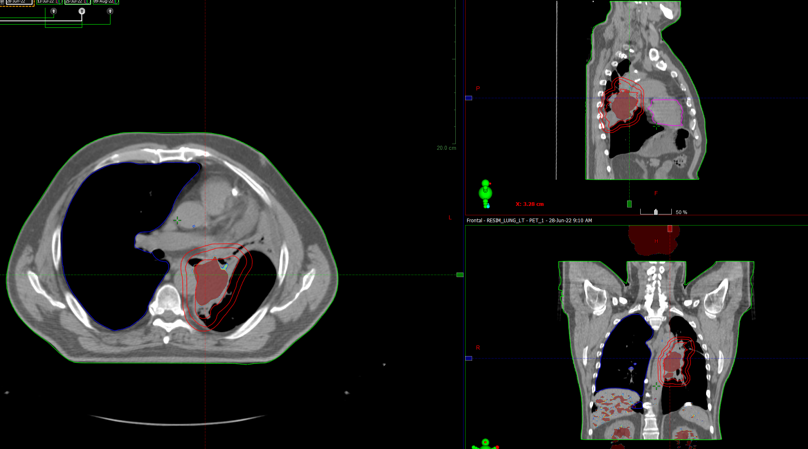

По данным ПЭТ-КТ с 18-ФДГ от 28.06.2022г. по сравнению с исследованием от 29.03.2022г. отмечается:

- уменьшение размеров с некоторым повышением метаболической активности образования в воротах левого легкого;

- уменьшение размеров и снижение метаболической активности медиастинальных лимфоузлов.

В воротах левого легкого сохраняется метаболически активный опухолевый узел с вовлечением главного, нижнедолевого, частично верхнедолевого бронхов, с некоторым уменьшение размеров и ростом метаболической активности, общими размерами около 60х38 мм SUVmax=24,72 (ранее до 83 мм в аксиальной проекции и до 81 мм в краниокаудальной проекции, SUVmax=21.41). Опухоль располагается на расстоянии около 30 мм от киля трахеи с вовлечением левой легочной артерии (обхват около 50%) и тесным прилеганием к нисходящей аорте. В правом легком очаговая и инфильтративная патология легких не определяется.Уменьшение размеров и снижение метаболической активности медиастинальных лимфоузлов, наибольшими размерами/накоплением РФП: подкаринальной группы (7) до 7 мм SUVmax=3,32 (ранее 10 мм, SUVmax=7.49); субаортальной группы (5) до 4 мм SUVmax=2,64 (ранее 8 мм, SUVmax=4.70). Лимфоузлы ворот левого легкого до 7 мм SUVmax=4,36 (ранее сливались с образованием).

В воротах левого легкого сохраняется метаболически активный опухолевый узел с вовлечением главного, нижнедолевого, частично верхнедолевого бронхов, с некоторым уменьшение размеров и ростом метаболической активности, общими размерами около 60х38 мм SUVmax=24,72 (ранее до 83 мм в аксиальной проекции и до 81 мм в краниокаудальной проекции, SUVmax=21.41). Опухоль располагается на расстоянии около 30 мм от киля трахеи с вовлечением левой легочной артерии (обхват около 50%) и тесным прилеганием к нисходящей аорте. В правом легком очаговая и инфильтративная патология легких не определяется.Уменьшение размеров и снижение метаболической активности медиастинальных лимфоузлов, наибольшими размерами/накоплением РФП: подкаринальной группы (7) до 7 мм SUVmax=3,32 (ранее 10 мм, SUVmax=7.49); субаортальной группы (5) до 4 мм SUVmax=2,64 (ранее 8 мм, SUVmax=4.70). Лимфоузлы ворот левого легкого до 7 мм SUVmax=4,36 (ранее сливались с образованием).

08.08.2022 на СОД 22 Гр выполнена повторная

КТ- топометрия органов грудной клетки

Курс химиолучевой терапии продолжен по плану